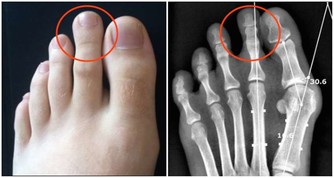

先說“痛”字,主要是發病時患者的關節會產生劇痛,就像身體的某個部位長出刺來一樣,想想就內心就覺得疼啊!再說“風”,這說明痛風也就是痛一會兒,時間不是很長,就像一陣風刮過之後,就沒了!

據流行病學的相關數據統計顯示,大約10%的高尿酸患者會發生痛風,痛風患者40%可繼發腎臟損害的表現!而且實際情況當中可比這個40%要高很多。